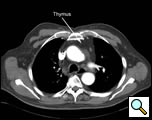

| Figure 1: CT scan of the chest with arrow pointing out the thymus gland. |

Thymectomy for myasthenia gravis, thymic cysts, thymoma less than two centimeters in size, and mediastinal parathyroid adenoma within the thymus are all indications for a video-assisted extended transcervical thymectomy (Figure 1). Thin, young female patients may be best suited for this approach, as they have a more pliable thoracic cage and less muscular chest wall compared to males. Patients who have had median sternotomy or prior radiation to the anterior mediastinum are not suitable for this approach due to adhesions that are present that prevent expansion of the anterior mediastinal space after placement of the sternal retractor, which is a requirement to perform the operation safely. Obesity is a relative contraindication to this approach, as the anterior mediastinal exposure is limited by body shape and fat and the ability of the sternal retractor to provide adequate exposure.